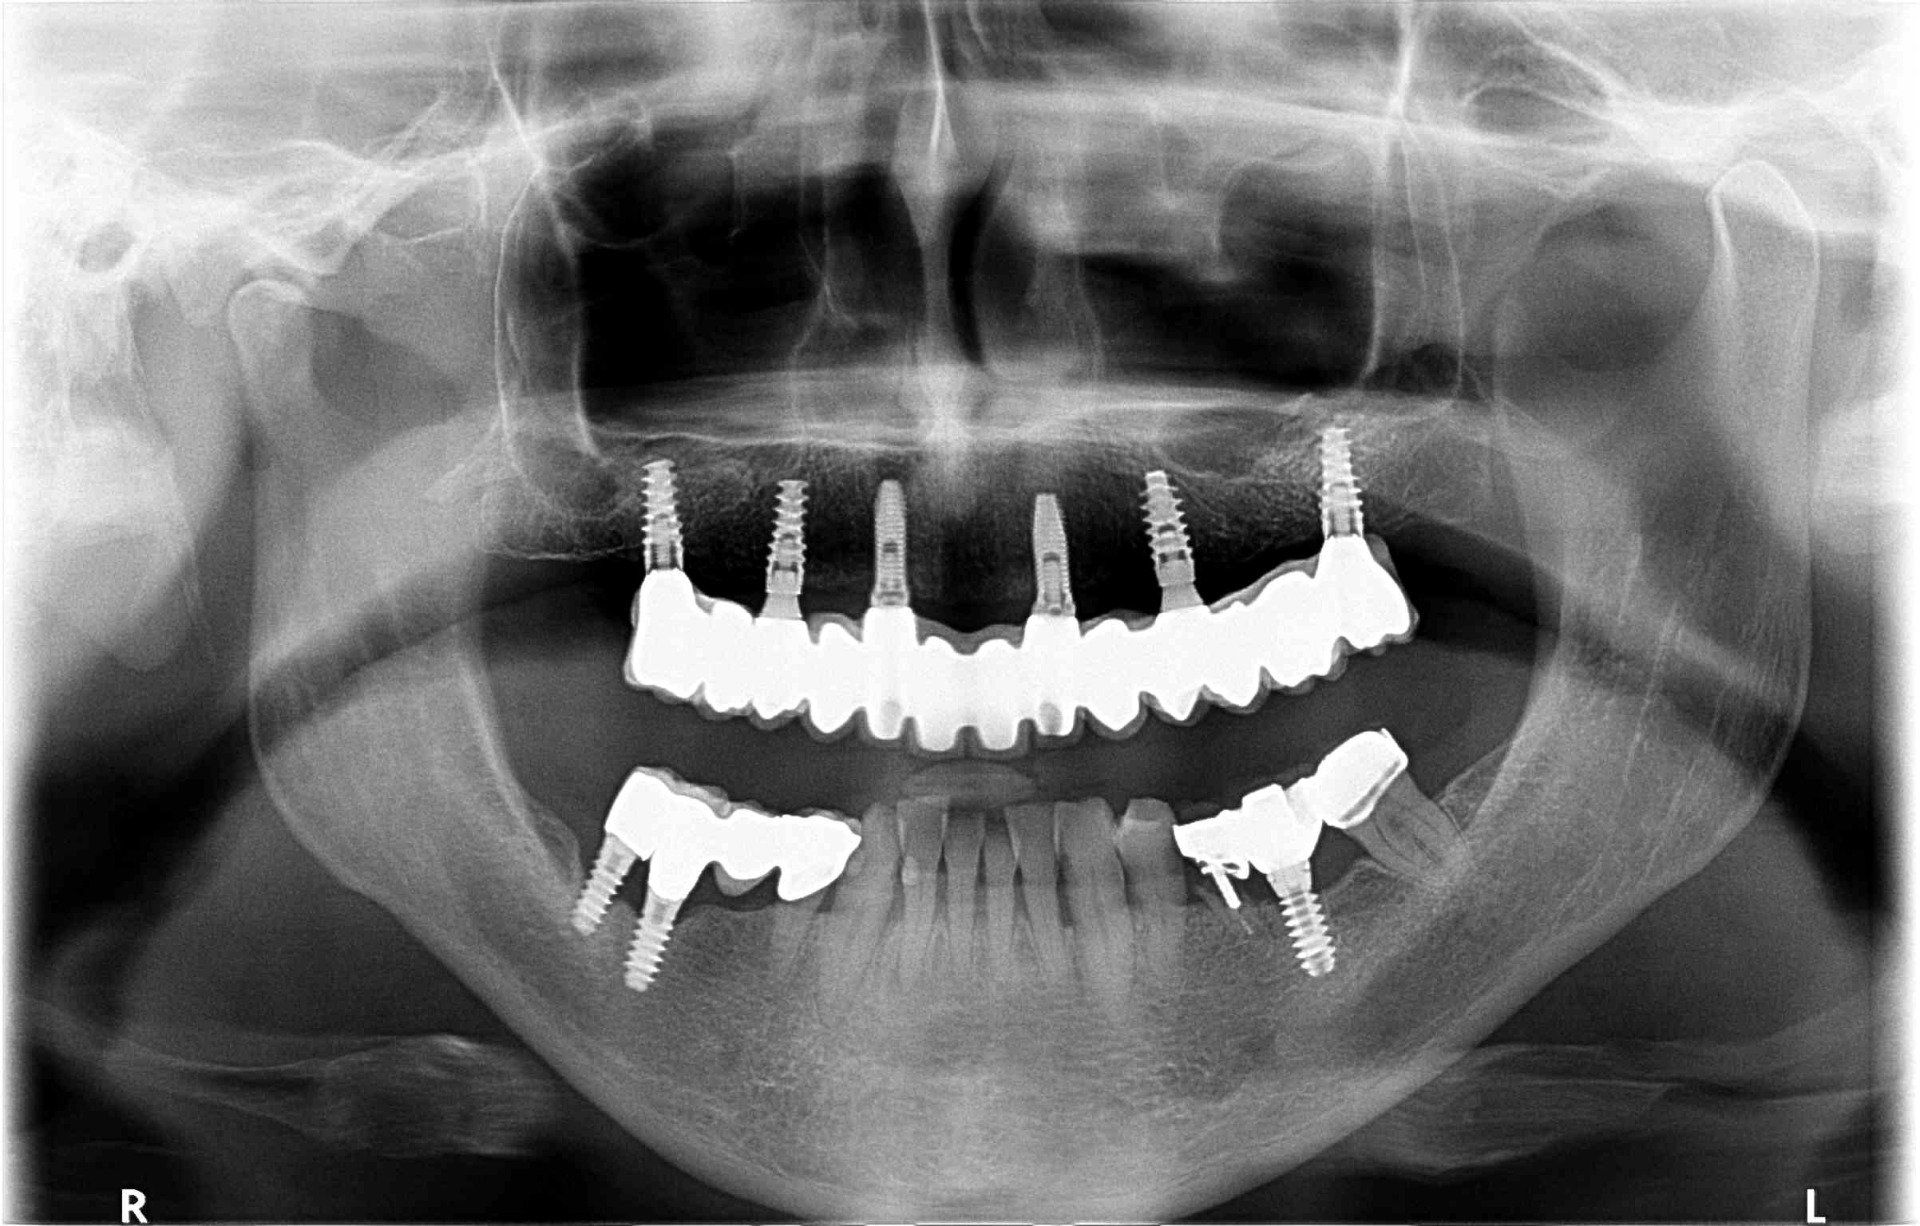

Oral implantology

Implantology is the dental specialty that deals with the replacement of the root of the lost tooth.

The replacement is done through a small surgical procedure to place a piece of titanium inside the jawbone.

The implant has a thread inside where the abutment that will support the prosthetic crown will later be screwed on.

After the evaluation of the implantologist and a very careful diagnosis by the professional team, different solutions are proposed. Depending on the problem posed, which may be: unit loss, multiple loss or complete edentulousness ... the precise technique will be performed in order to improve the quality of life of the patient.

The Center Odontològic Piñera has a state-of-the-art radiological equipment that allows to perform orthopantomography (x-rays of the whole mouth), dental CBCT and intraoral dental scanner in 3D (3 dimensions). Radiological exposure is minimal.

This technology favors the speed of the examination, as well as the precision in the diagnosis and the subsequent treatment.